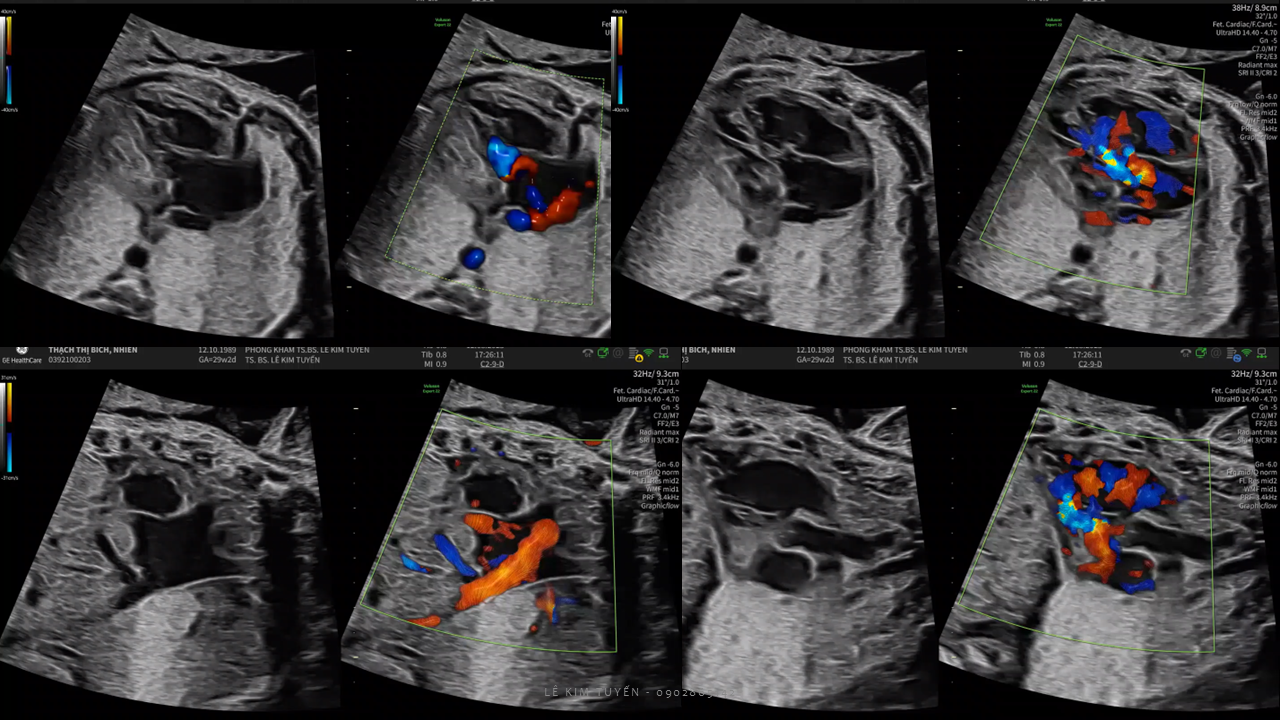

Siêu âm tim thai - Các kỹ thuật hiện đại

TS. BS. Lê Kim Tuyến

Bệnh viện Tim Tâm Đức